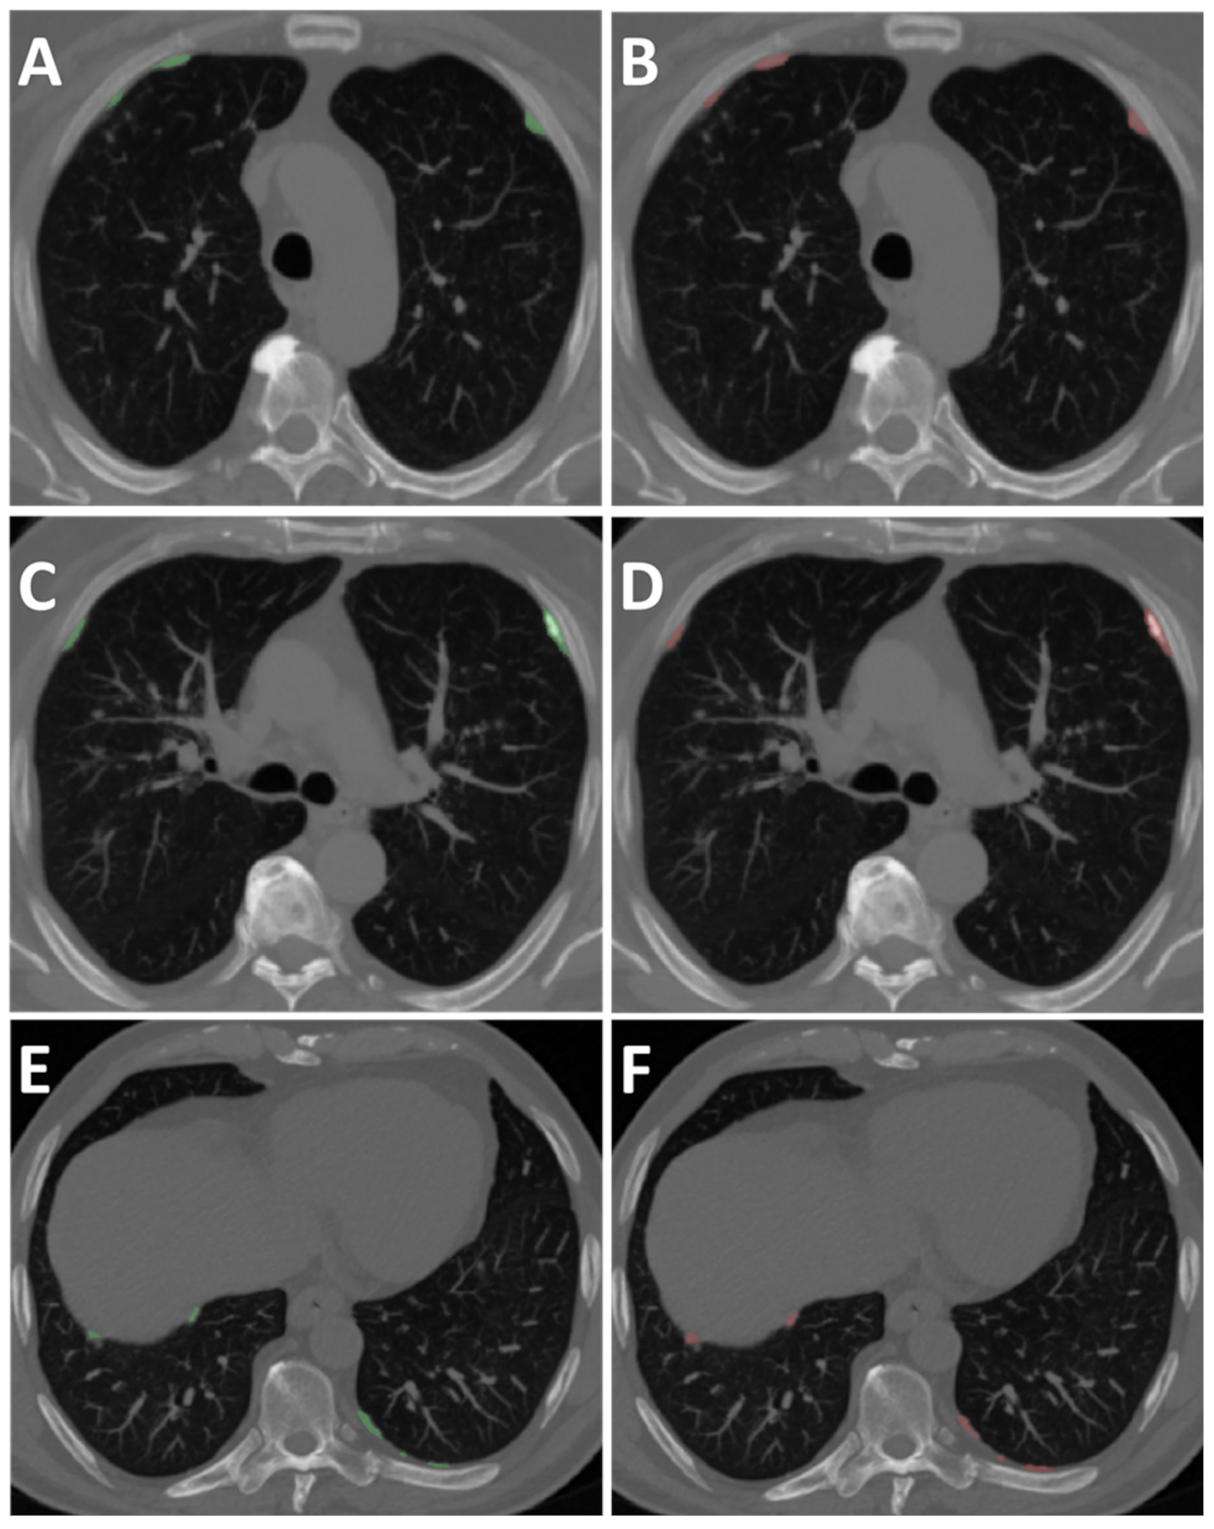

2.4. Data

2.5. Chest CT Scans Visual Analysis

2.6. AI Training Framework